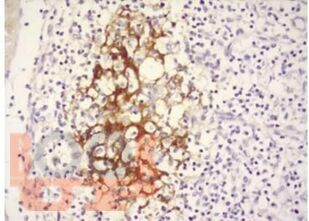

Представлены основные современные сведения по врожденным инфекциям, встречающимся в практике врача педиатра, инфекциониста, неонатолога и оказывающим влияние на беременность, плод и новорожденного ребенка. Особое внимание уделено вопросам эпидемиологии, иммунопатогенеза, клинической картины и лабораторной диагностики, также основным принципам комплексной терапии, профилактики и реабилитации детей с врожденными инфекциями. Обобщены основные сведения по клинической картине, диагностике и лечению рекомендательного характера, определяющих тактику врача с учетом диспансерного наблюдения в декретированные сроки. Авторами сделан акцент на клинические случаи различных нозологических форм врожденной инфекции, с полным клинико-лабораторным спектром обследования и тактикой ведения этих пациентов. Для самоконтроля даны тестовые задания и ситуационные задачи, решение, которых предполагается на практических занятиях.